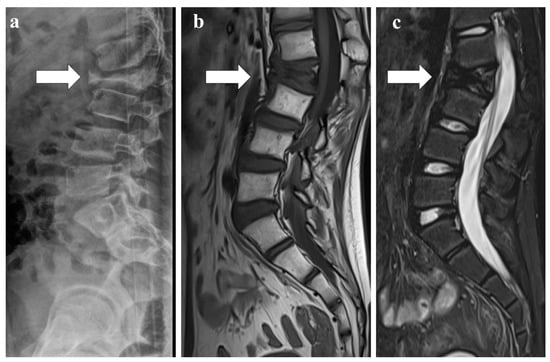

Infections